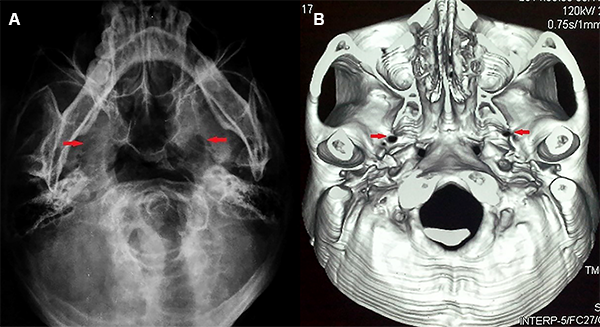

La resonancia magnética de encéfalo fue realizada con una combinación de tres secuencias de alta resolución (3D ponderada en T2, 3D TOF-MRA y 3D T1-Gad) para la detección de un posible contacto neurovascular con cortes finos en los nervios trigéminos. Los agujeros ovales fueron evaluados con radiografías o tomografía computarizada de base cráneo (Figura 2A y 2B).

Figura 2:

(A) Radiografía en incidencia de submento-vértical. (B) Tomografía computarizada con reconstrucción 3D de base del cráneo. Las flechas muestran los agujeros ovales.